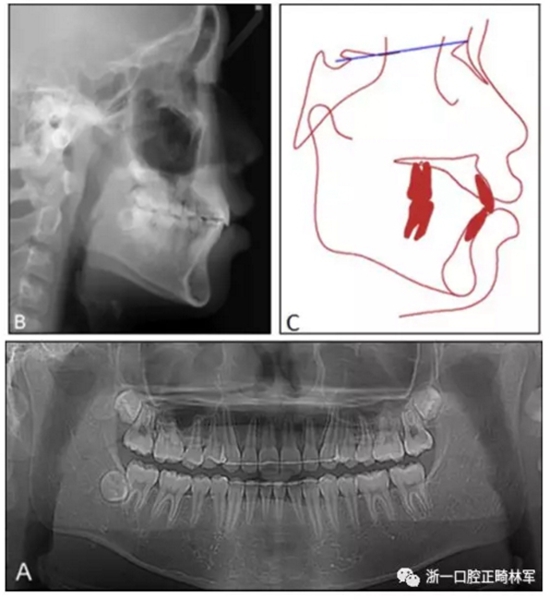

患者面型得到較大改善,治療后開(kāi)唇露齒解決,側(cè)貌突度減小?;颊叩母埠细采w恢復(fù)正常,磨牙關(guān)系與尖牙關(guān)系維持I類(lèi)。

治療后全景片上示牙根平行度可,無(wú)明顯牙根吸收。側(cè)位片示,上頜切牙直立(U1-FH,從121°變?yōu)?07°),鼻唇角增加,從86°變?yōu)?01.5°。在重疊圖中可見(jiàn),上頜切牙與磨牙分別后移了2.5mm與3mm,下頜平面角減小了1°,合平面角增加了2°。

10個(gè)月后復(fù)查,療效穩(wěn)定,無(wú)明顯復(fù)發(fā)。